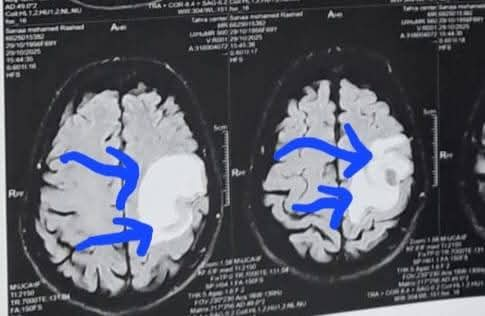

تعود تفاصيل الحالة إلى استقبال المستشفى المريضة بالعيادة الخارجية وهي تشكو من تنميل وضعف بالجانب الأيمن وثقل بسيط في الكلام، وبإجراء الفحوصات اللازمة من أشعة مقطعية ورنين مغناطيسي بالصبغة، تبين وجود ورم بالمخ، وتم إعطاؤها العلاج المناسب لحين استكمال الفحوصات.

ودخلت المريضة غرفة العمليات، حيث أُجريت جراحة مخ دقيقة شملت فتح عظام الجمجمة، وفصل الورم تدريجيًا عن أنسجة المخ مع السيطرة على الأوعية الدموية المغذية له.